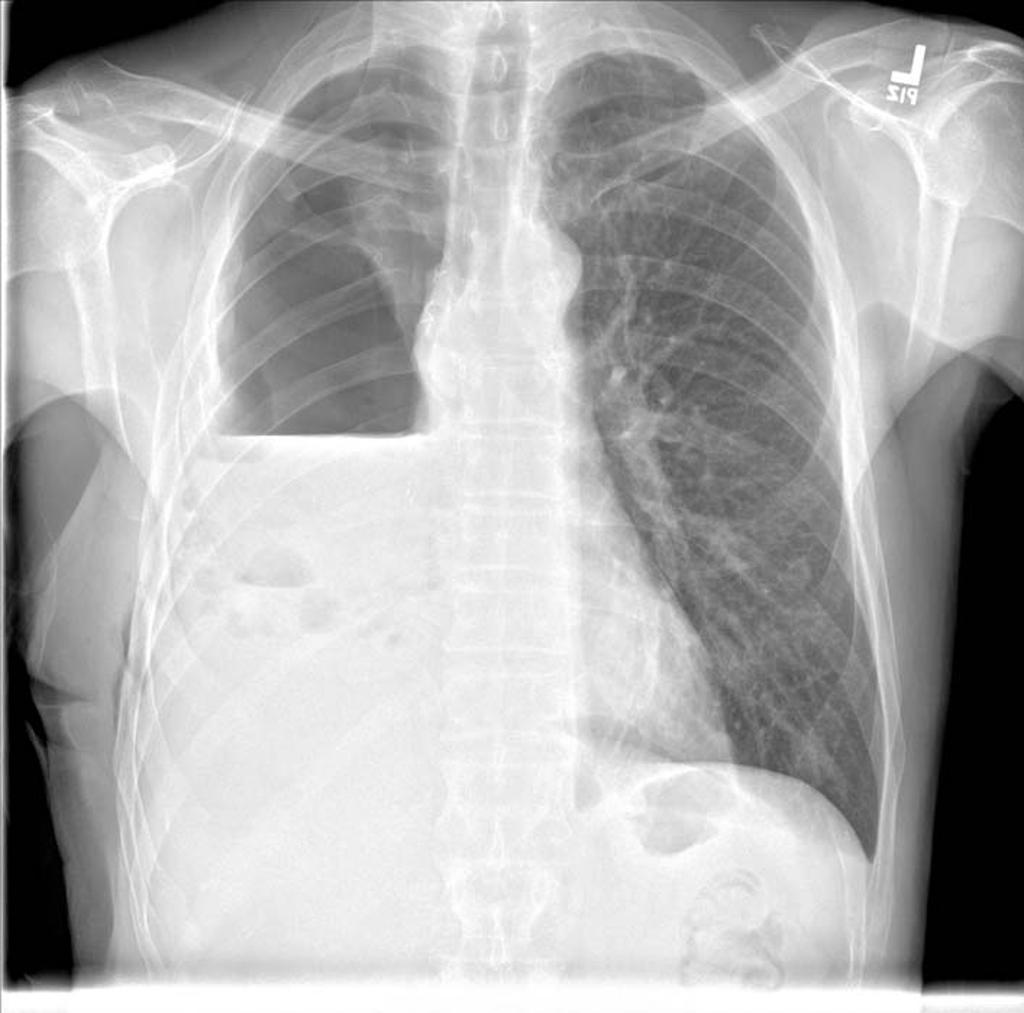

Bonus Points: 75M Chest PainĀ